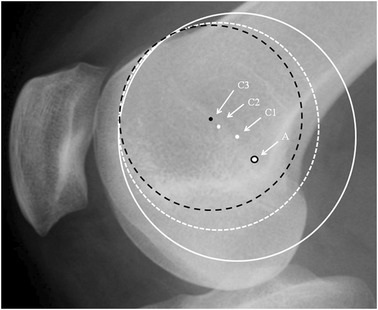

It was noticeable that when applying a circle to the groove line in the PFI cohort, the circle could be placed to touch two points on the groove, e.g., B and D (Fig. 3) or the circle could match much of the groove (Fig. 4). In the control cohort the groove matched a circle. In Fig. 3, for a patient with TD, it can be seen that the isometric point is anterior to Schöttle’s point, and the radius of the circle from Schöttle’s point to the apex of the boss is longer than that for the best-fit circle. This would result in a significantly anisometric graft if the Schöttle’s point was used as the femoral tunnel position. In Fig. 4, in TD, isometric point moves anteriorly as the circle is made smaller. This implies that there is potential for significant error in the isometric point position in TD. A much more complex methodology is needed requiring 3D reconstruction and analysis of the tracking of the patella to define the femoral tunnel position in the presence of TD. This is not appropriate for the surgeon in a clinic. Interestingly, using 3D CT scans in different degrees of knee flexion, Blatter et al. [4] only found one isometric point in 10 normal knees when measuring the MPFL length with a maximal length difference during knee flexion of 10 mm. They also noted that for most, the optimal tunnel position was slightly anterior to Schöttle’s point. It would be interesting to know how this correlated with the lateral plain radiograph.

Lateral radiograph of the knee showing different circles depending on how the observer chooses the best circle-fit to the dysplastic trochlea curve: Schöttle’s point: black rimmed spot (A). Centres of white circles: white spot (C1) solid circle and (C2) dashed circle. Centre of black circle: black spot (C3)